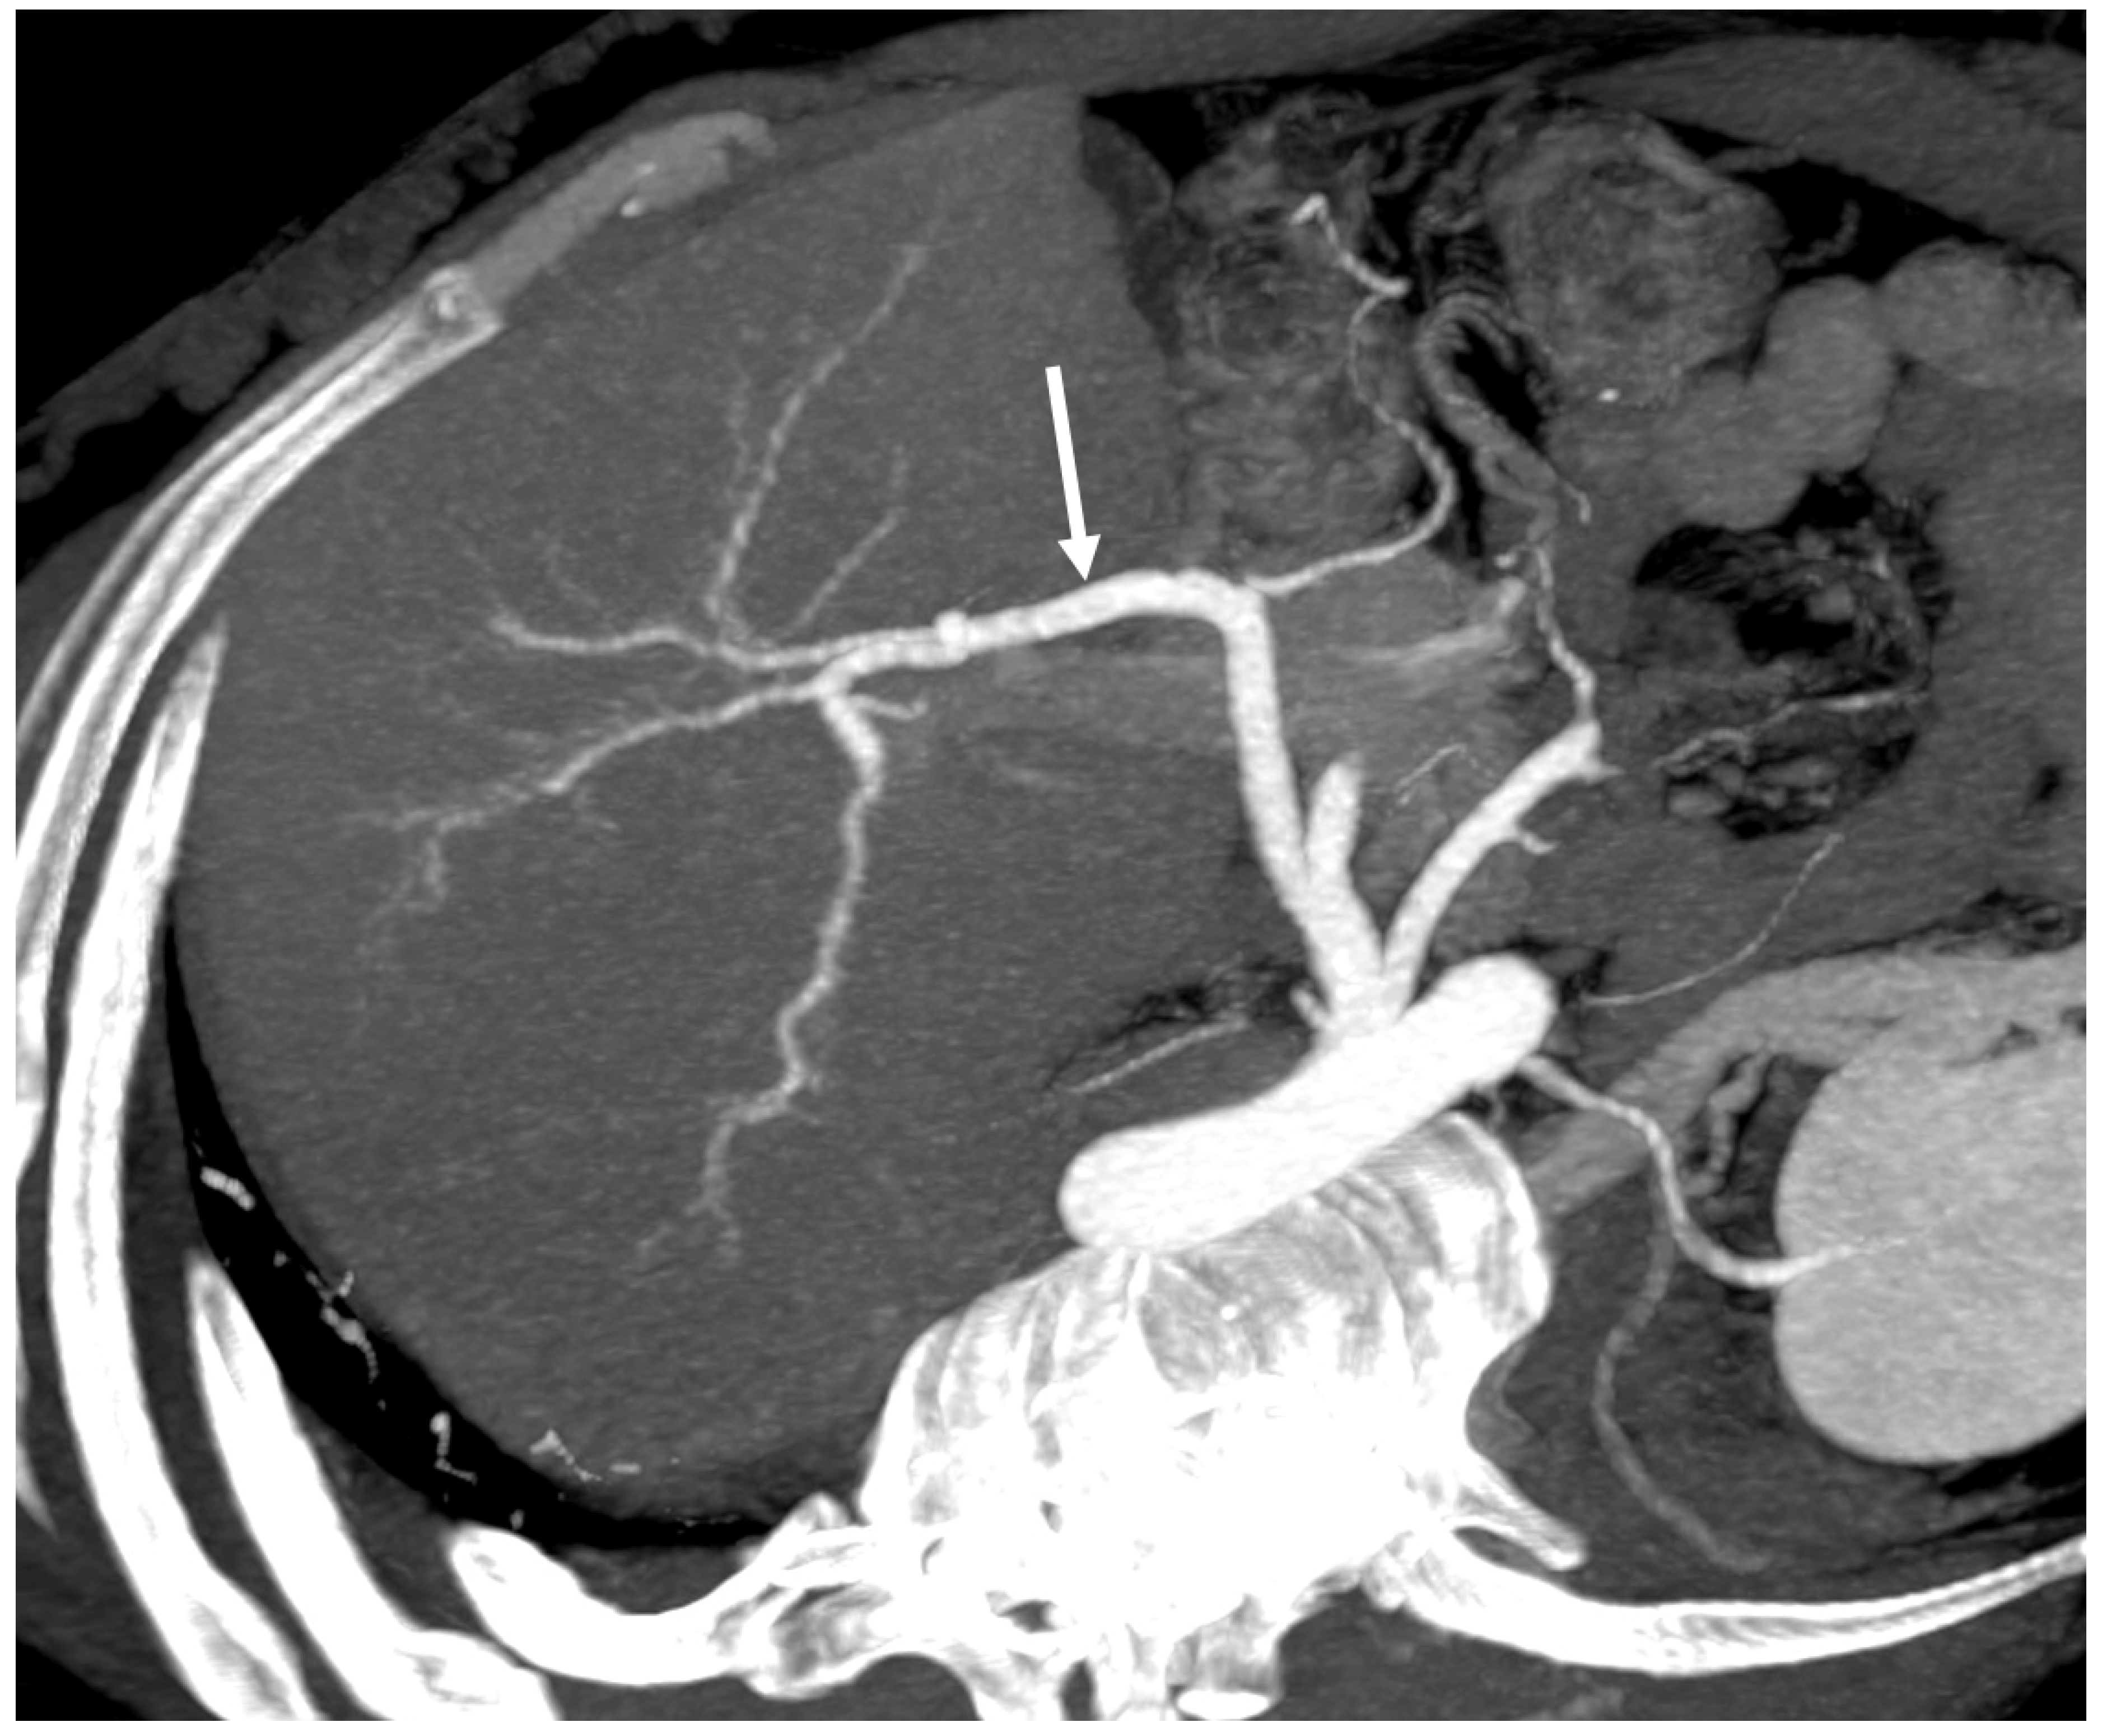

3.2. Computed Tomography and Magnetic Resonance: What to Look For

| CT | Liver morphology alteration Acute phase: “zonal” or “flip-flop” perfusion Chronic phase: “mosaic” perfusion Extra- and intra-hepatic collaterals Site and extension of thrombosis Pre-endovascular treatment assessment Hepatic artery and caudate vein enlargement Hepatic Nodules Ascites and caudal lobe enlargement |